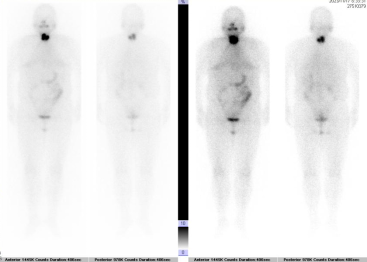

碘131全身显像(甲状腺癌术后,颈部原甲状腺区域少许残留甲状腺组织显影):